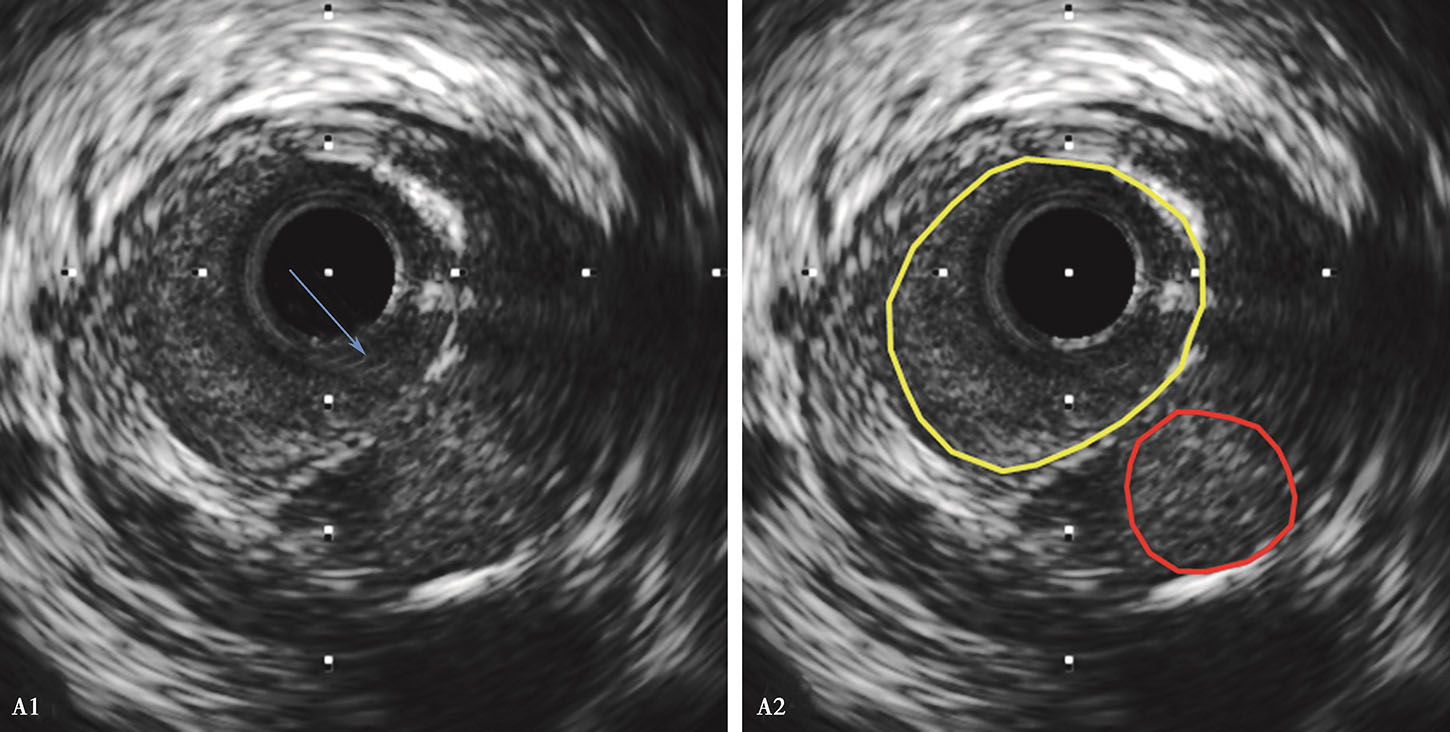

冠状动脉血管内超声成像_挂云帆

图片尺寸736x355